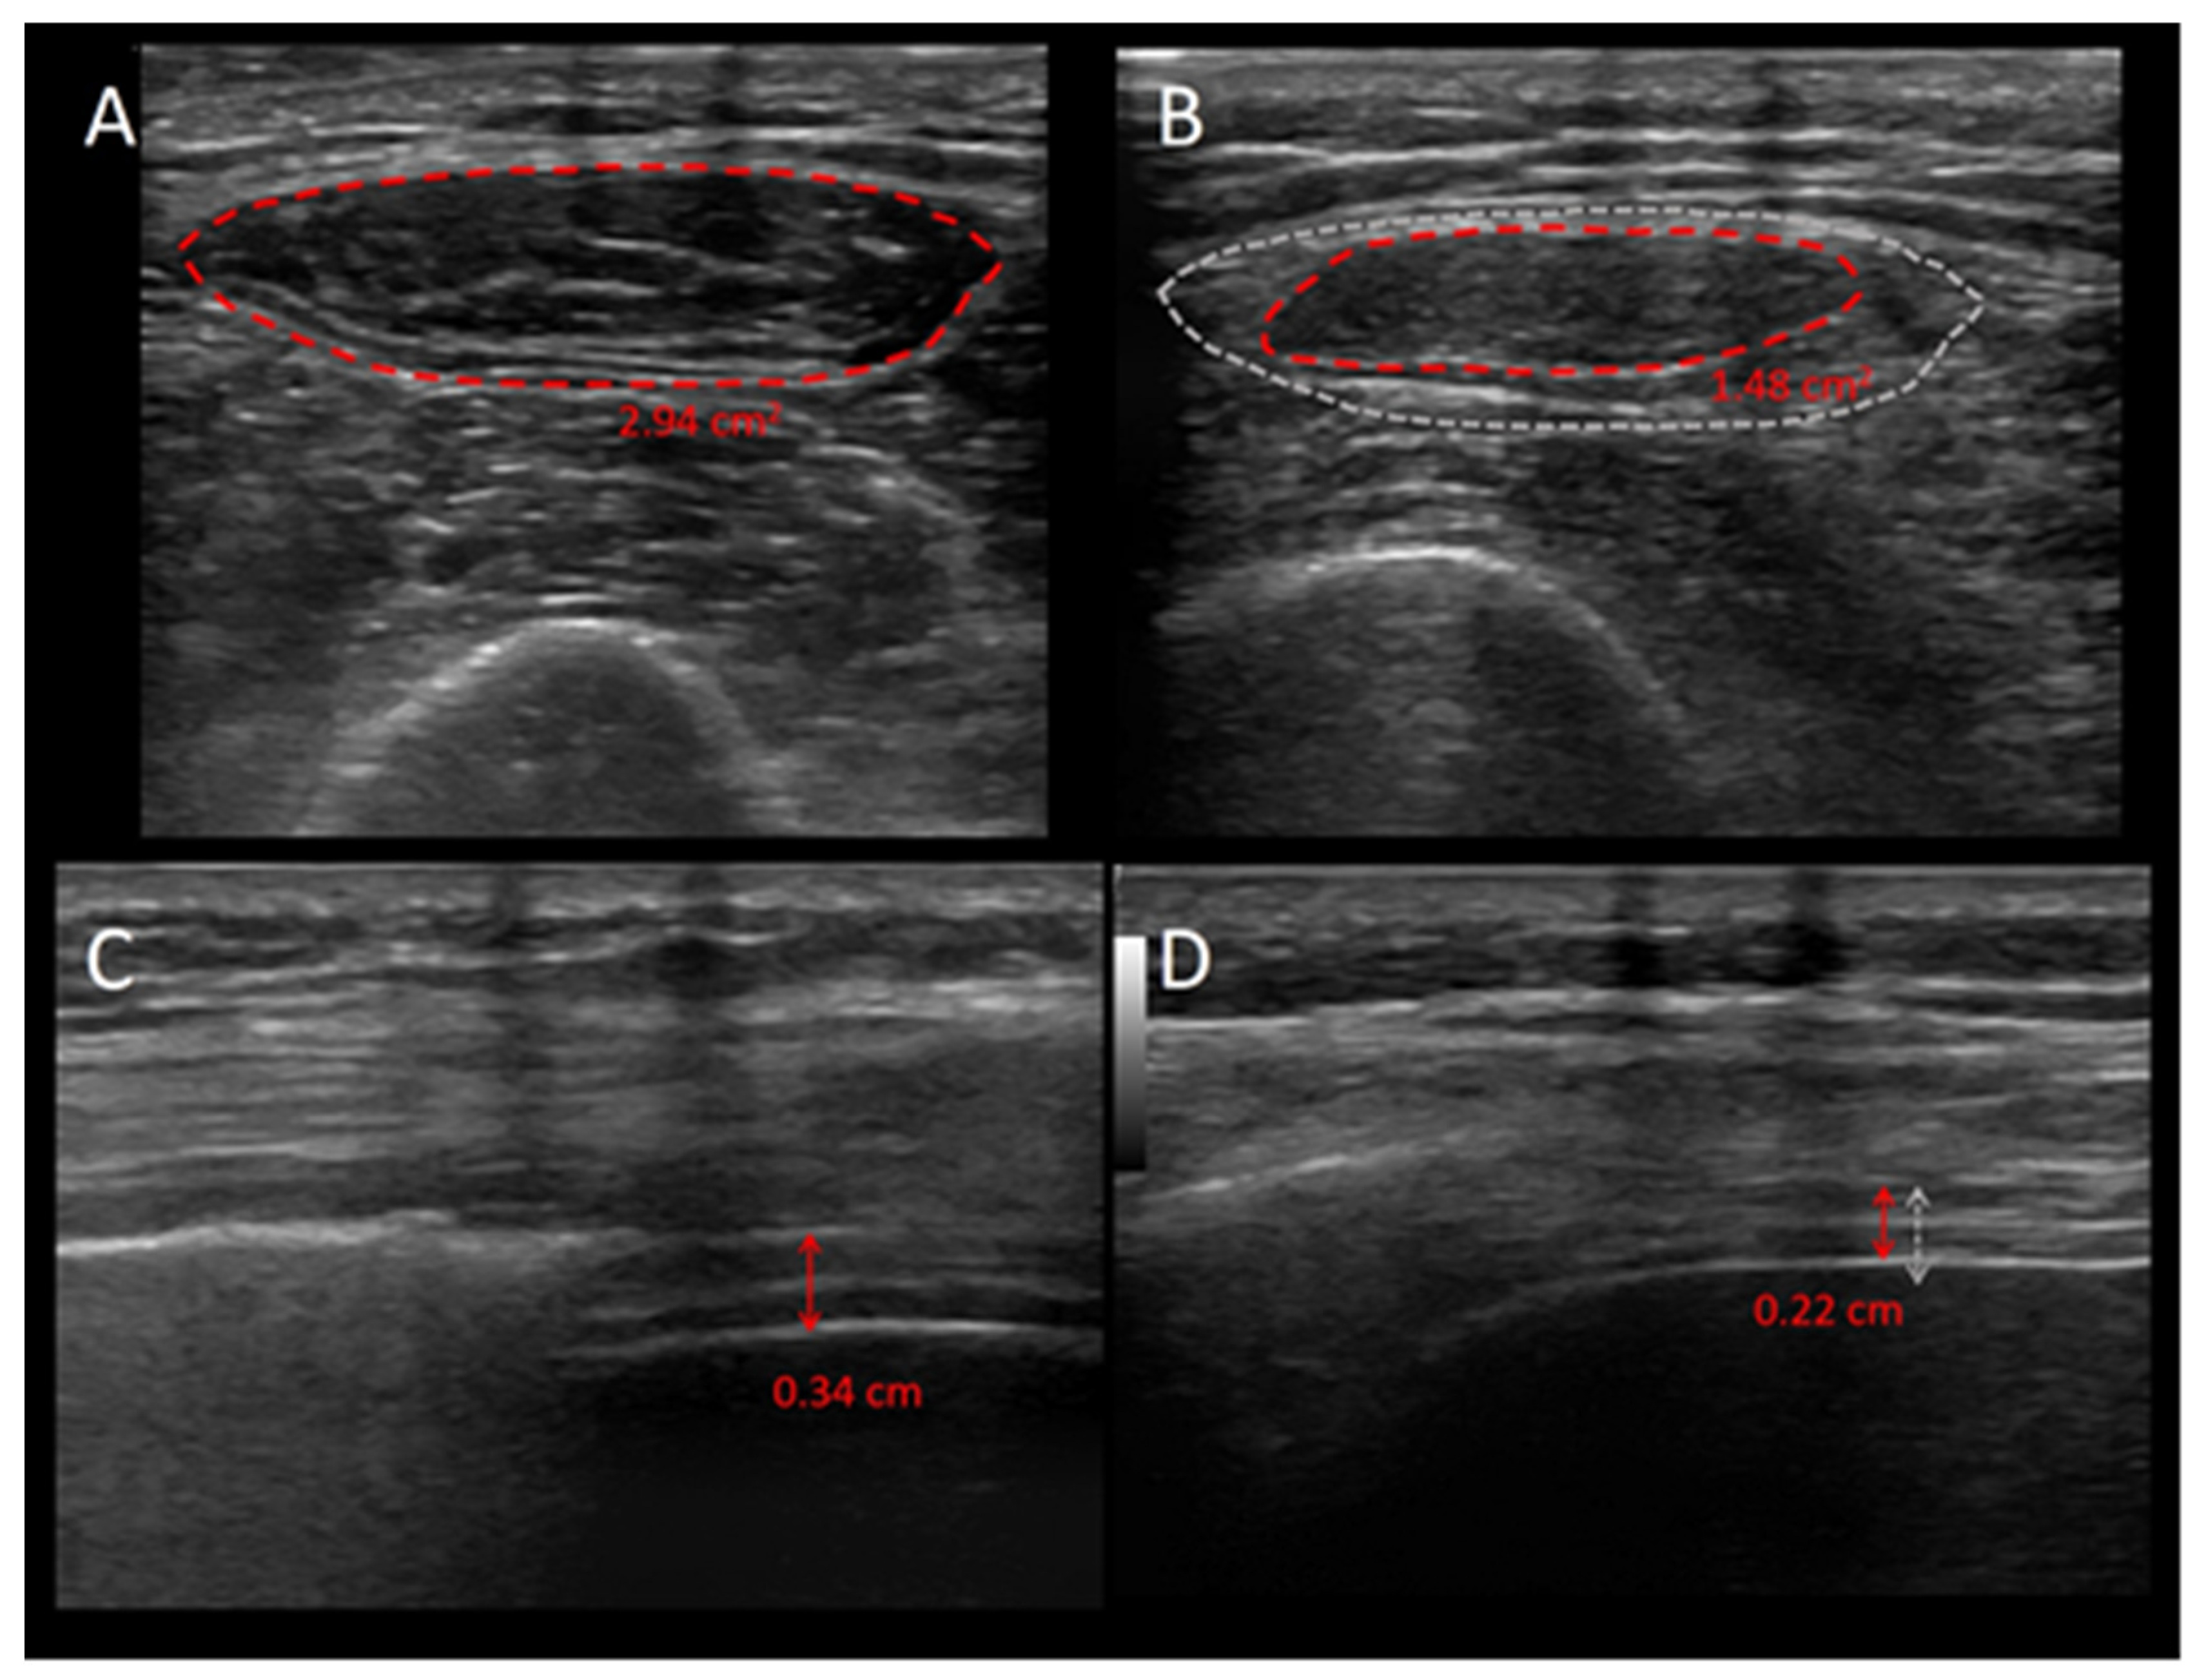

- Mourtzakis, M.; Parry, S.; Connolly, B.; Puthucheary, Z. Skeletal Muscle Ultrasound in Critical Care: A Tool in Need of Translation. Ann. Am. Thorac. Soc. 2017, 14, 1495–1503. [Google Scholar] [CrossRef]

- Formenti, P.; Umbrello, M.; Coppola, S.; Froio, S.; Chiumello, D. Clinical review: Peripheral muscular ultrasound in the ICU. Ann. Intensive Care 2019, 9, 57. [Google Scholar] [CrossRef]

- Hammond, K.; Mampilly, J.; Laghi, F.A.; Goyal, A.; Collins, E.G.; McBurney, C.; Jubran, A.; Tobin, M.J. Validity and reliability of rectus femoris ultrasound measurements: Comparison of curved-array and linear-array transducers. J. Rehabil. Res. Dev. 2014, 51, 1155–1164. [Google Scholar] [CrossRef] [PubMed]

- Parry, S.M.; El-Ansary, D.; Cartwright, M.S.; Sarwal, A.; Berney, S.; Koopman, R.; Annoni, R.; Puthucheary, Z.; Gordon, I.R.; Morris, P.E.; et al. Ultrasonography in the intensive care setting can be used to detect changes in the quality and quantity of muscle and is related to muscle strength and function. J. Crit. Care. 2015, 30, e9–e14. [Google Scholar] [CrossRef]